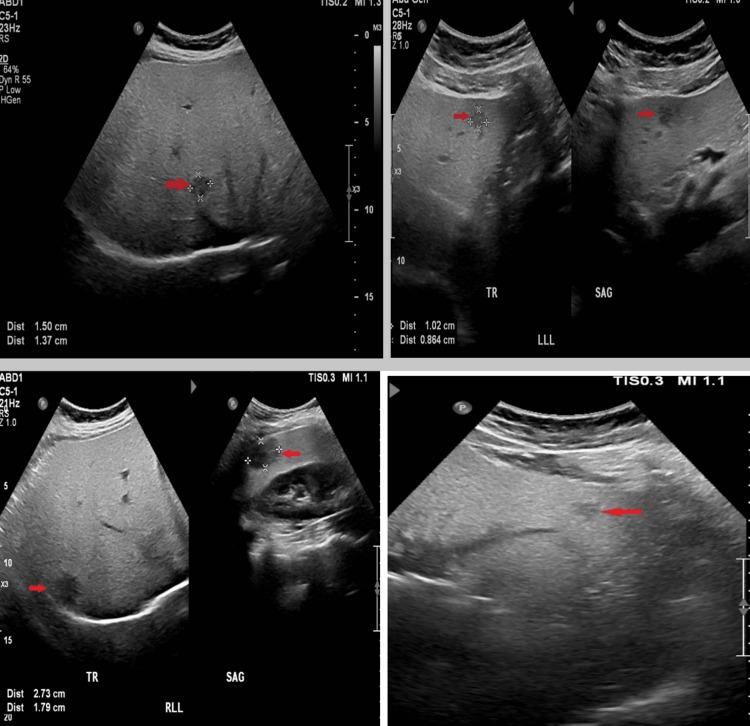

Hepatic steatosis is frequent; however, it may present with unusual patterns, resulting in a diagnostic dilemma. Herein, we present a case of fatty liver and multifocal nodular hepatic lesions that were found to be due to multifocal nodular fatty sparing, which mimics metastasis or primary multifocal tumors. As the differential diagnosis of such lesions can be difficult based on ultrasound alone, the knowledge of Magnetic Resonance Imaging (MRI) findings is crucial. It enables the radiologists to make the correct diagnosis and alleviate the patient from unnecessary biopsies.

肝脂肪变性很常见;然而,它可能呈现出不寻常的模式,导致诊断困境。在此,我们报告一例脂肪肝和多灶性肝结节性病变的病例,结果发现是多灶性结节性脂肪 sparing,它模仿转移瘤或原发性多灶性肿瘤。由于仅基于超声对这些病变进行鉴别诊断可能很困难,了解磁共振成像(MRI)表现至关重要。这使放射科医生能够做出正确诊断,并使患者免于不必要的活检。